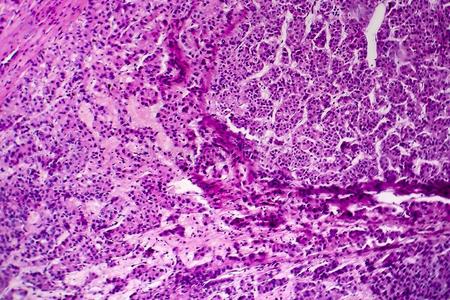

肝细胞癌镜下观

肝细胞癌,显微镜下的hcc